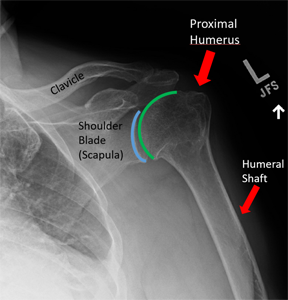

어깨뼈 골절 수술 후, 입원 중에는 주로 진통제가 투여되어 통증을 관리합니다. 이로써 입원 중에는 통증이 그리 심하지 않게 느껴질 수 있습니다. 상완골 골절의 경우 핀고정 수술이 주로 시행되며, 수술 후에는 상완골의 고정이 유지됩니다.